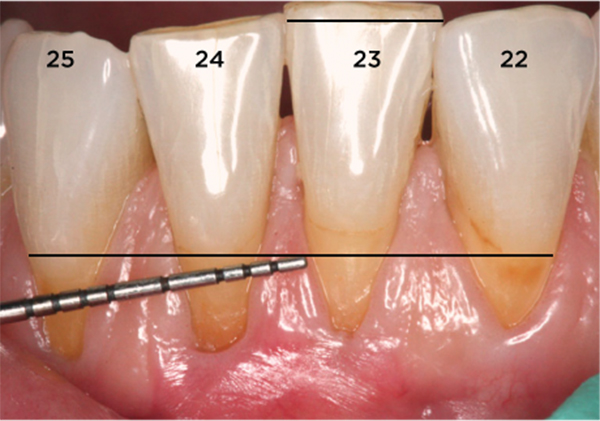

La recesión dental ocurre cuando la encía se retrae y deja expuesta parte de la raíz del diente. Esta exposición puede causar sensibilidad dental, molestias estéticas e incluso aumentar el riesgo de caries en la raíz o pérdida del diente si no se trata a tiempo.

✅ Encías retraídas o dientes que “lucen más largos”

Dependiendo del caso, el tratamiento puede ser tan sencillo como ajustar la técnica de cepillado, o bien requerir procedimientos como injertos de encía para recuperar el tejido perdido.